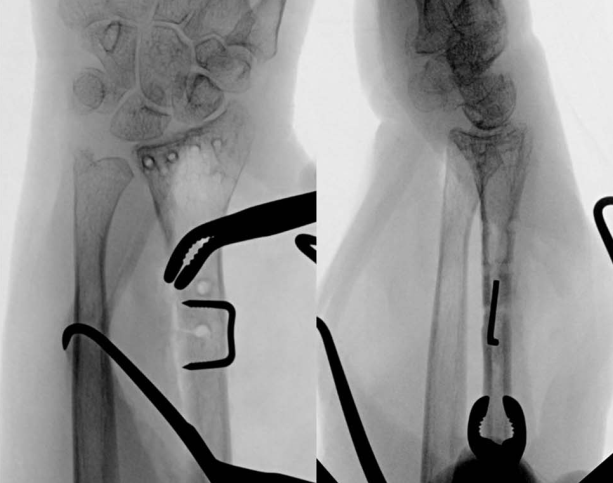

与肱骨干骨折相似,在桡骨干横行骨折的固定中,也可采用骑缝钉临时固定后,再通过钢板螺钉系统确切固定: